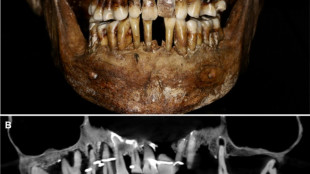

French aristocrat's golden dental secret revealed 400 years on